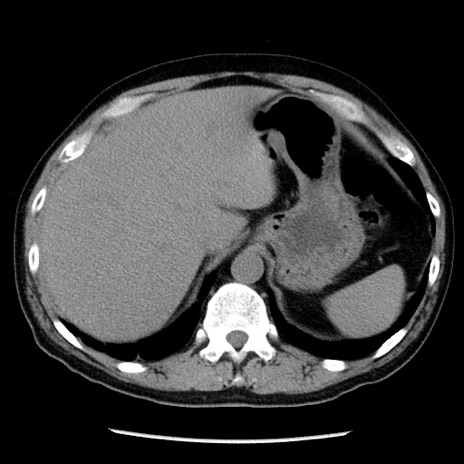

冠状断像